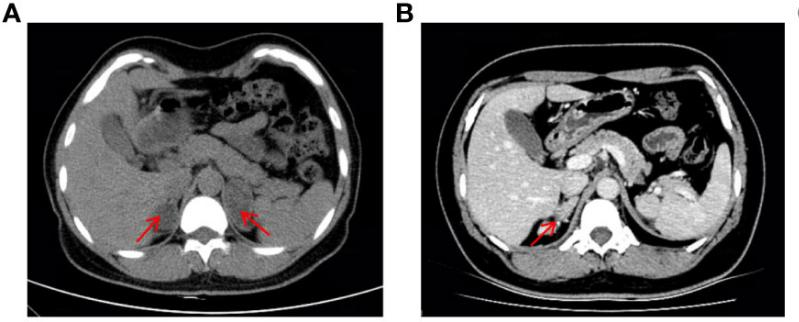

该患者是一名37岁的女性(核型为46,XX),童年时保存生长加速,且婚后一直未有身。2019年因疑诊双侧肾上腺肿瘤入院(图1A),前后举行了两次肾上腺切除术。2022年,患者由于月经不规则被收入内渗透科,CT显示右肾上腺皮质增生复发(图1B),体格检查显示该患者皮肤色素冷静,面部有痤疮和髯毛,泛起男性化体征,生化检查提醒低钾性高血压,高雄血症。均提醒11β-OHD诊断。

图1  患者腹部CT影像